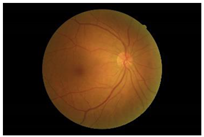

Diabetes is characterised by hyperglycaemia and impaired carbohydrate, lipid, and protein metabolism related with absolute or relative insulin activity or secretion [1]. The estimated worldwide prevalence of diabetes in 2019 was 9.3% (463 million people), and in 2045 is expected to continue to increase to 10.9% (700 million people) [2]. Hyperglycaemia that is not well controlled can lead to complications of diabetes, such as nephropathy, retinopathy, neuropathy, and cardiovascular disease [3]. The most common complication is diabetic retinopathy (DR), a significant cause of visual impairment, especially in the younger and economically active age group. It usually occurs due to the appearance of a series of lesions on the retina characterised by changes in capillary microaneurysms (MAs), capillary degeneration, vascular permeability, and abnormal production of blood vessels [3]. More than 4 million people experience sight loss due to DR, of which 3.3 million have moderate-to-severe visual impairment and the rest are blind [4]. There are two main classes of DR, namely, non-proliferative diabetic retinopathy (NPDR) and proliferative diabetic retinopathy (PDR) [5]. NPDR has lesions, such as the appearance of MAs, haemorrhages (HMs), and hard exudates (EXs) on the retina. Meanwhile, PDR is the more advanced stage of DR characterised by neovascularisation or abnormal blood vessel development [5,6]. Figure 1 presents the fundus images.

Figure 1.

Fundus images.